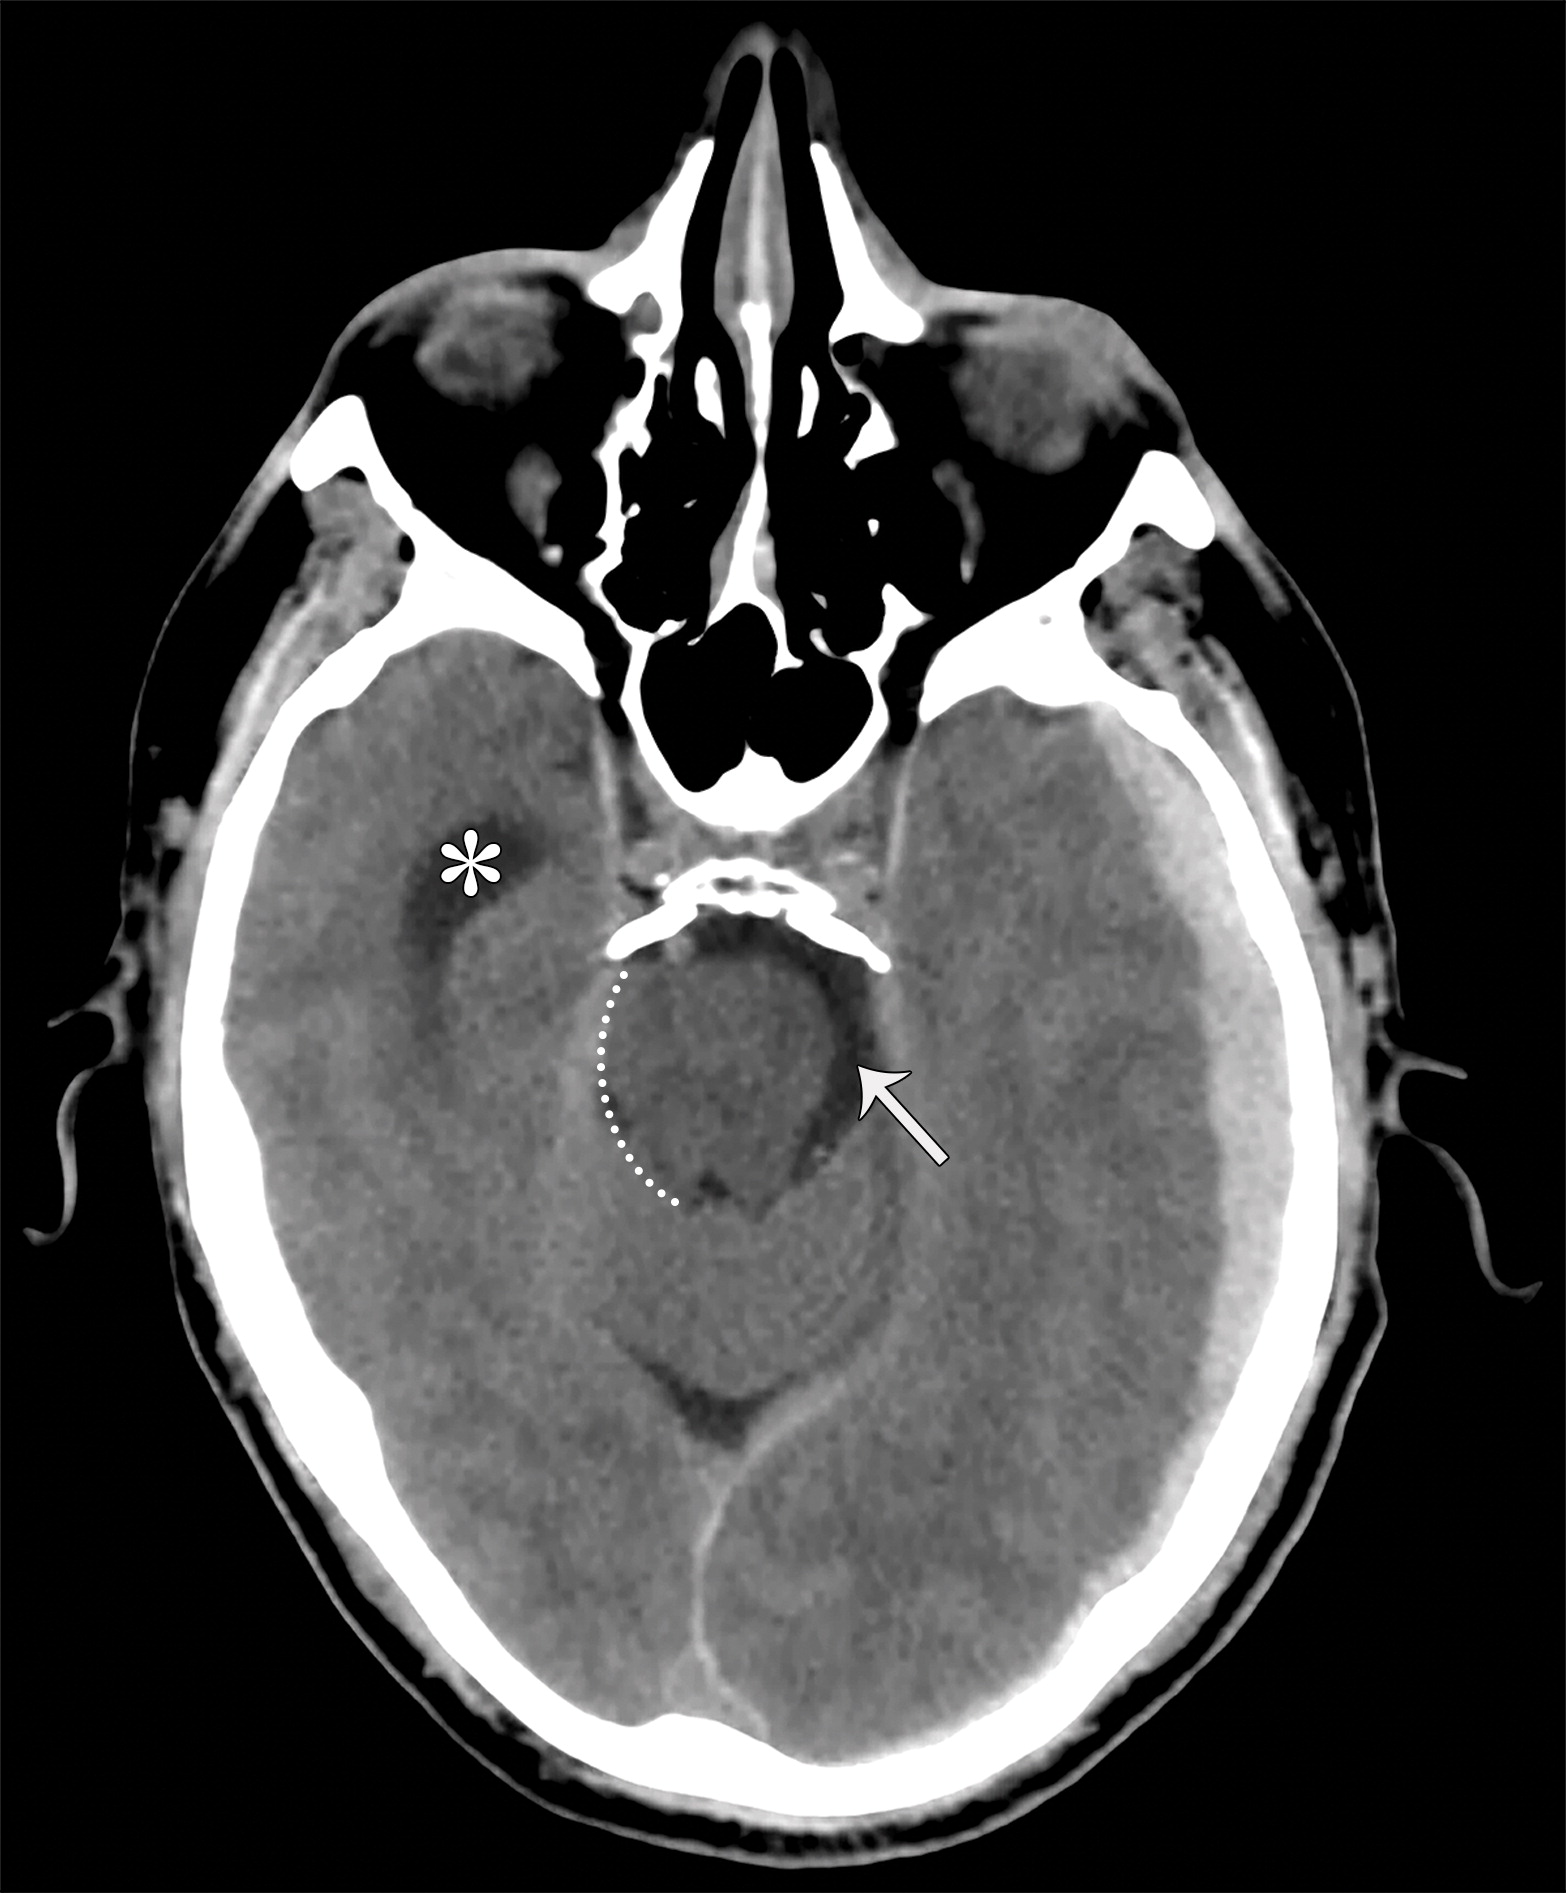

2a4f468a04150c279dbe4187672a609d.jpeg

大脑镰下疝。平扫轴位CT示:右侧硬膜下血肿(*)伴混合密度影,表明处于不同时期的血液,血肿推挤使透明隔相对于中线(白色虚线)向左侧移位(白色长箭头)。右侧侧脑室受压,但是左侧侧脑室扩张。